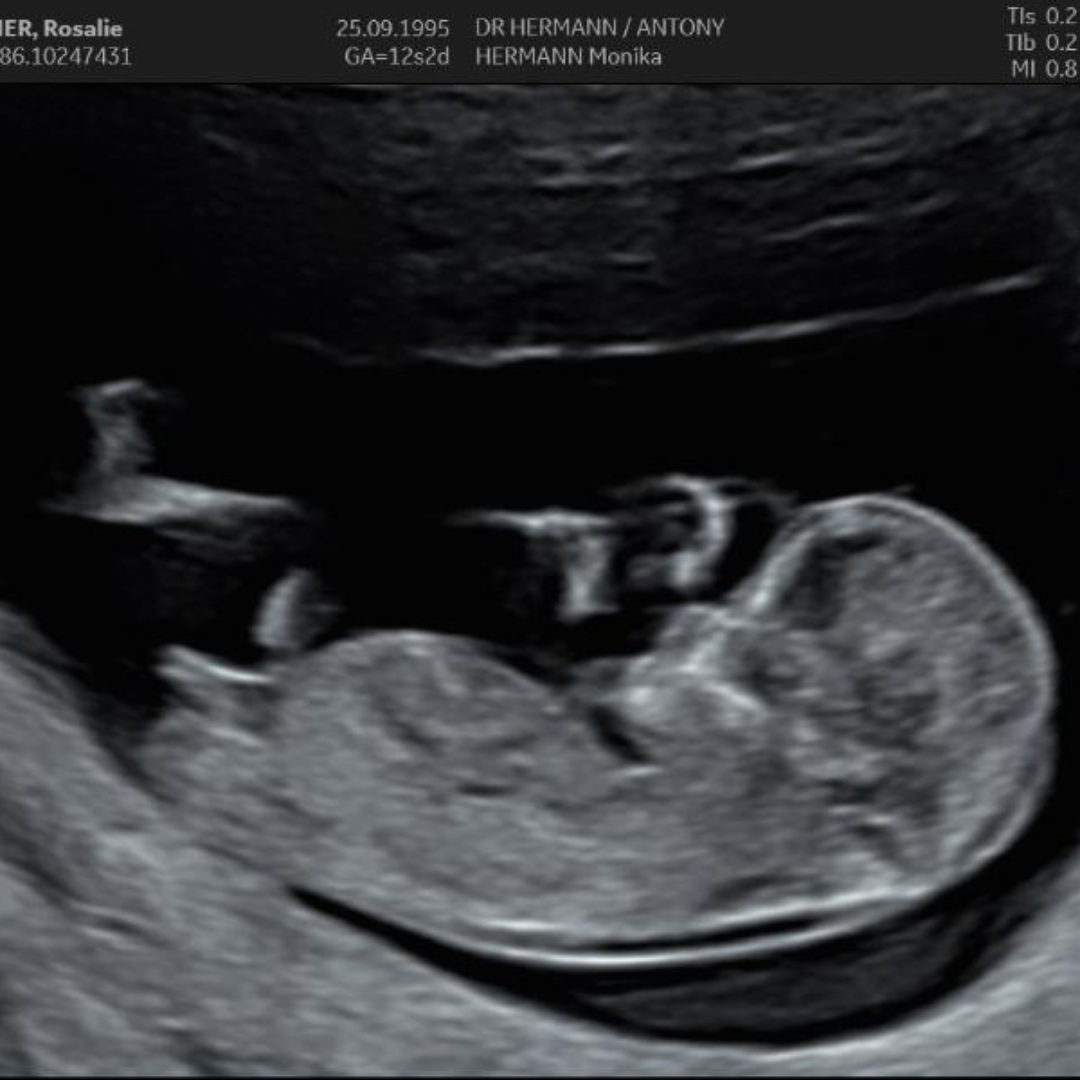

Suite de l'histoire